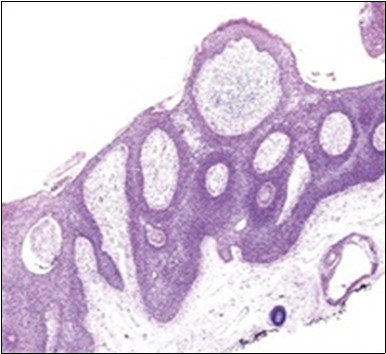

Granular arrangement of malignant cells and intercellular bridges are conspicuous with the demonstration of nuclear atypia, pleomorphism, prominent mitosis and tumour necrosis. A peripheral palisade is discernible within the cellular aggregates. Mitotic figures are common and can be quantified as up to 12 mitosis/ high power field. Tumour differentiation can prominently be of the ductal category with the demonstration of intra-cytoplasmic lumina. Comedo type tumour necrosis is evident along with foci of squamous differentiation The neoplasm is reactive to periodic acid Schiff ‘s (PAS) stain. (Figure 1, Figure 2, Figure 3, Figure 4, Figure 5, Figure 6, Figure 7, Figure 8, Figure 9, Figure 10, Figure 11, Figure 12, Figure 13.

Figure 2.Epidermal projections lined with atypical and malignant epithelial cells in eccrine porocarcinoma (14).